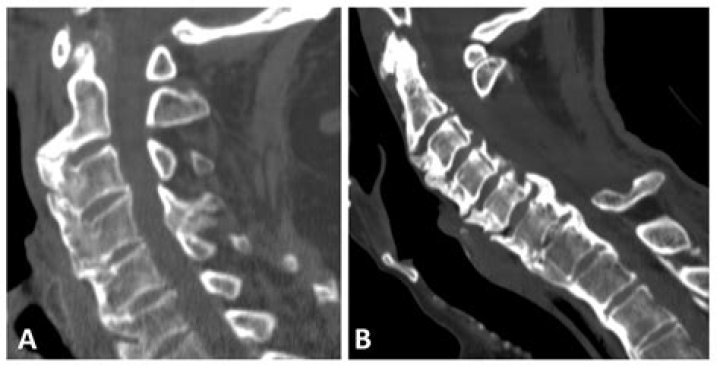

internal auditory canal HCI is a hereditary bone disorder characterized by progressive skull-base osteosclerosis and endosteal hyperostosis of the calvaria (Fig 1).

Discussion. In HCI, endosteal hyperostosis occurs in the parietal, frontal, occipital, sphenoid, ethmoid, and temporal bones without obliteration of the diploe. The most marked change is thickening of the inner table of the calvaria, except for the parietal region, where broadening of the diploe is more explicit.